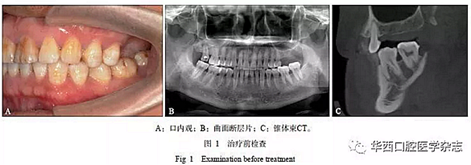

患者男性,45歲,2015年10月由四川大學(xué)華西口腔醫(yī)院種植科轉(zhuǎn)診,主訴“左上后牙缺失,種植前要求壓低左下后牙”??趦?nèi)檢查見(jiàn)上下牙列無(wú)擁擠,25與35牙為中性關(guān)系,26、27牙缺失,36、37牙伸長(zhǎng)(圖1A)。

1)正畸治療前完善影像學(xué)檢查(圖1B、C)及牙周基礎(chǔ)治療;